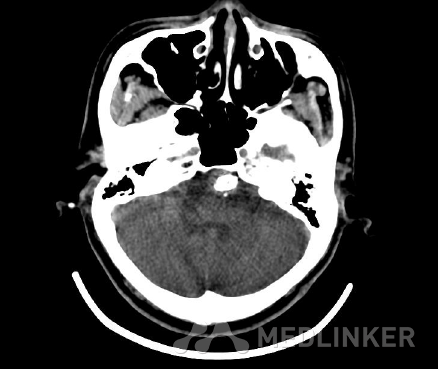

后颅窝延及鞍上池左侧部见支架影及较重伪影,脑干左前方见血管瘤样较高密度影,请结合 临床、对照以往资料;余部脑实质内未见异常密度灶。

诊断:1,椎基底动脉延长扩张症并巨大血栓形成;2,基底动脉供血不足。3、高血压病 诊治经过:入院后完善相关检查,于8月20日在静脉全麻下行主动脉弓造影十全脑血管造影+支架植入术。术 后予以抗凝,抗血小板等对症处理。